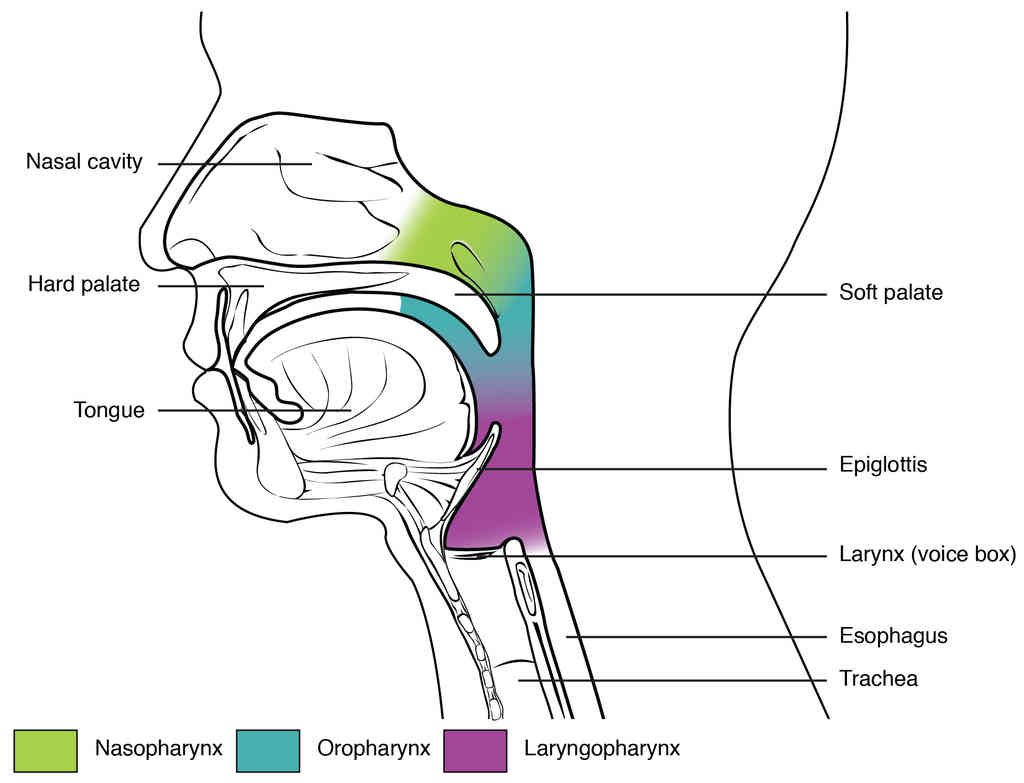

This page is under construction. For now, it is just a resource of the images found in the OpenStax Anatomy and Physiology Handbook. It wil slowly change into a revision tool. Each slide has a number. Use this to refer to the slide. When completed, it will have an unlabelled section, with labelled slides in parallel. On the unlabelled slides, write your answer and use the labelled slide to assess yourself. Keep track by also noting the number on each slide. Improvement at each attempt is important, more so than full marks on a first attempt.